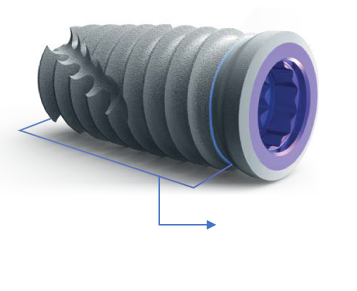

El implante T3® PRO de ZimVie® es la versión de nueva generación del implante cónico, diseñado para ofrecer una alta estabilidad primaria y posibilidad de función inmediata, reduciendo los tiempos de tratamiento sin sacrificar los resultados estéticos ni la salud ósea a largo plazo.

Su ingeniería incluye un núcleo totalmente cónico con roscado progresivamente más profundo hacia el ápice, lo que permite un contacto inicial hueso-implante alto y una inserción controlada. Además, cuenta con una superficie híbrida contemporánea, destinada a favorecer la osteointegración y mantener el nivel óseo periimplantario.

El sistema conserva la conexión interna Certain® compatible con la tecnología SureSeal™ y “Platform Switching”, lo que asegura un sello fuerte entre implante y pilar. Esto ayuda a minimizar micromovimientos o filtraciones, factores importantes para la durabilidad y salud del implante.

DISEÑO HÍBRIDO CONTEMPORÁNEO

Estabilidad primaria

El contacto inicial entre el hueso y el implante es el principal responsable de la estabilidad del implante. Las especificaciones de los implantes T3® de ZimVie® están sujetos a rigurosas tolerancias para ofrecer un íntimo ajuste entre el implante y la osteotomia, creando un sistema de implantes dentales que ayuda a conseguir estabilidad primaria.